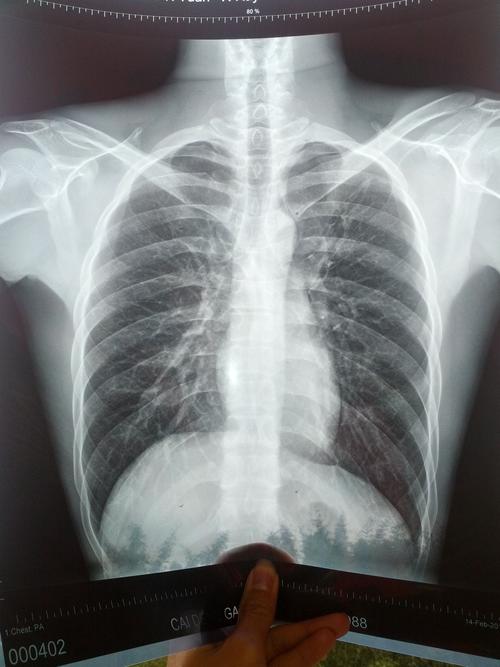

做x胸片多久可以怀孕

拍片子后多久可以怀孕,这是很多人比较关心的问题。拍片后,有很多人关心对方的时间。因为拍片后是需要注意一些事项的。那么,拍片子后多久可以怀孕呢?接下来,小编就为大家详细介绍一下这方面的内容。